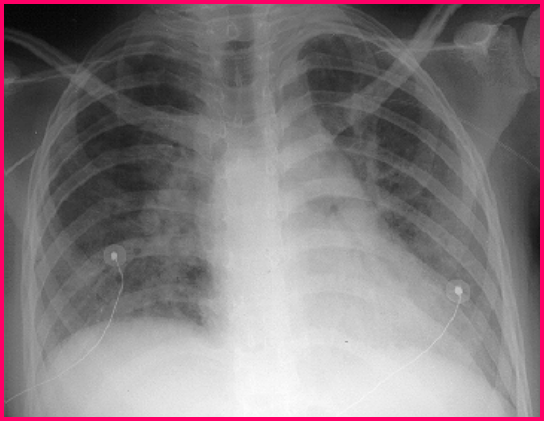

白色念珠菌肺炎

(candida pneumonia)

4 岁女孩患感染性肉芽肿,

合并肺炎。卧位胸部 X 线

检查见:

-双侧致密中等大小班片阴影

-右侧肺门大片致密阴影

-肺部透亮度增加,尤其是基底部